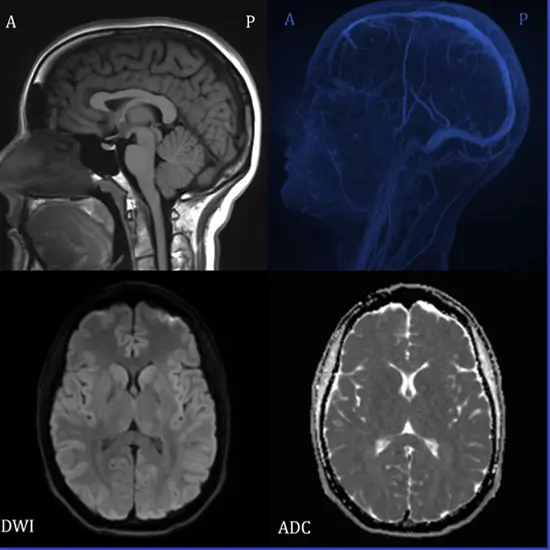

MRI BRAIN + DWI is a procedure in which it uses specific MRI sequences and software that produces images from the resulting data that utilize the diffusion of water molecules to produce contrast in MR images.

MRI Brain DWI is an MRI technique that helps to measure molecular diffusion in biological tissues. It is conducted to detect acute ischemic stroke and differentiation of acute stroke from other developments that occur with sudden neurologic deficits.

In this procedure, DWI is combined with perfusion MRI, and outlines salvageable areas of ischemia and MR angiography. It provides a valuable guide for stroke management. For standard neuroimaging application, b-values up to 1000 are used.